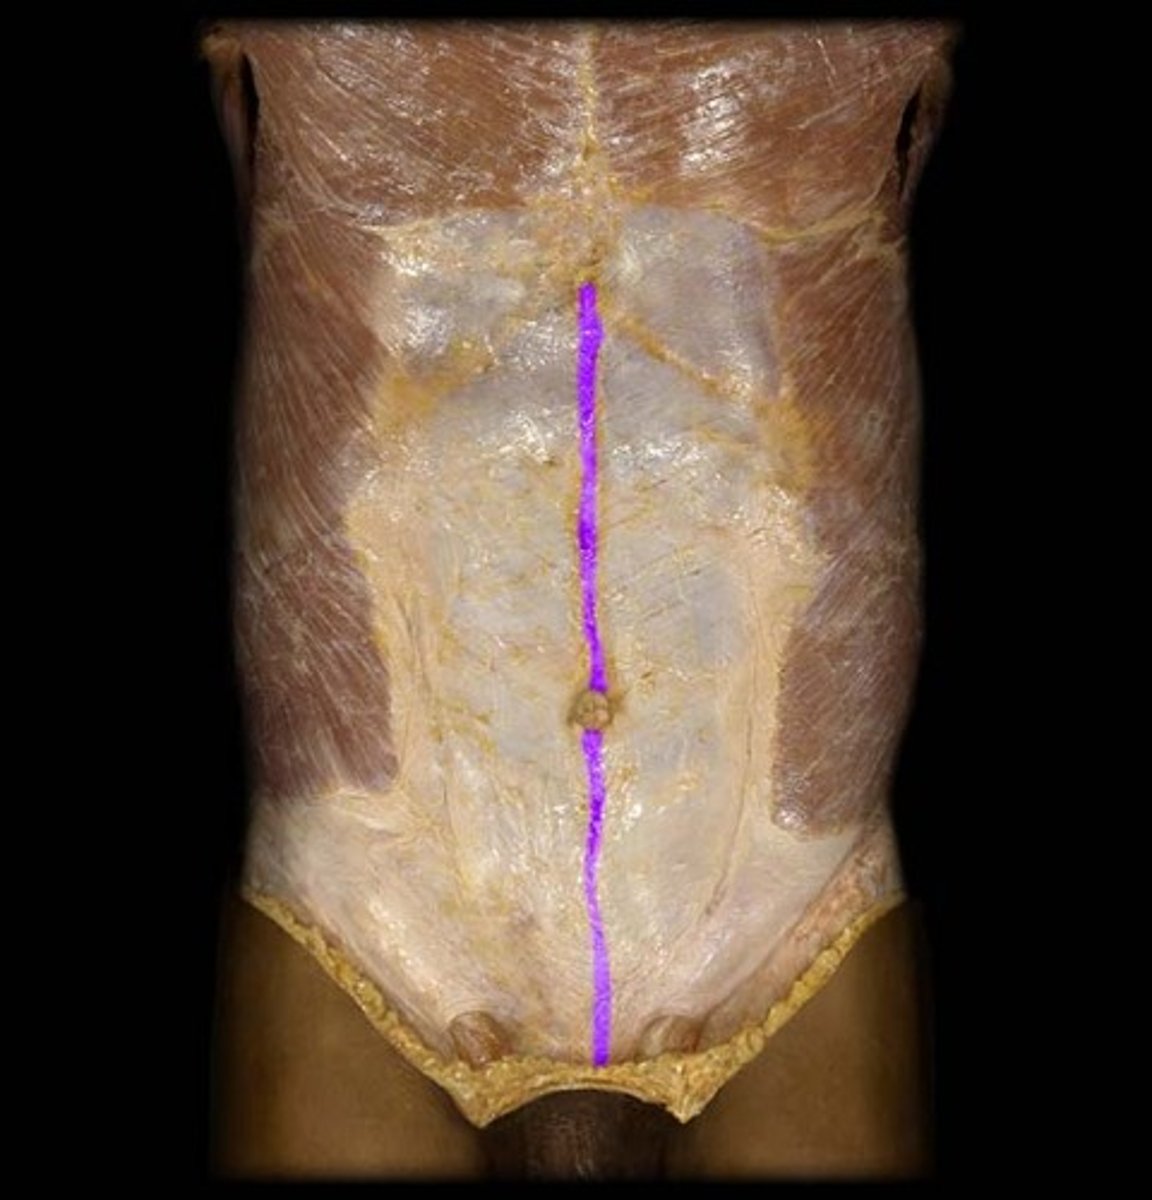

Rectus Abdominus

Origin: Pubic symphysis and superior margin of pubis

Insertion: Xiphoid process; costal cartilages 5-7

Action: flexes trunk, stabilizes pelvic region during walking, and compresses abdominal viscera

Linea Alba

Non-muscular, fiberous structure running between xiphoid process and pubic symphysis

Insertion: site for transverse abdominis